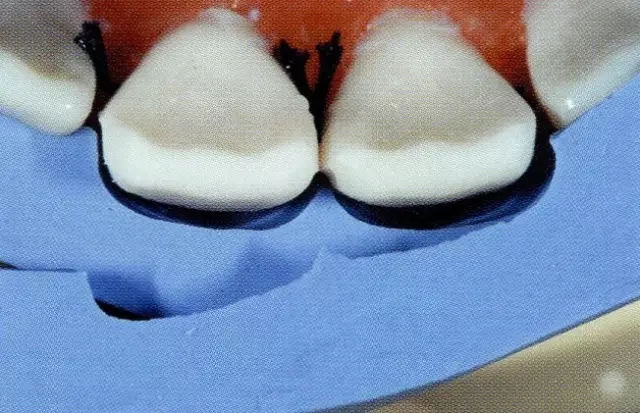

另外,貼面也是不是日常臨床中經(jīng)??梢宰龅?,它也與全覆蓋冠和嵌體等不同,所以牙體預(yù)備上很多處理都讓人丈二和尚摸不著頭腦。想必這個(gè)很多醫(yī)生都經(jīng)歷過,在修整預(yù)備好的牙體時(shí)會(huì)有制備過度的問題。(圖1)

圖1 失敗的牙體預(yù)備。用硅橡膠模型確認(rèn),得出右上1的唇側(cè)打磨量過多。